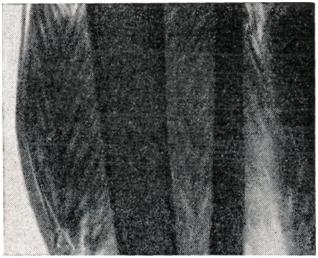

Газовая гангрена. Газ в мышцах. Рисунок «ёлочки» (рентгенограмма).

Рентгенодиагностика, Очень убедительные диагностические данные можно получить с помощью рентгенографии. Она позволяет обнаружить такое ничтожное количество газа, которое не удается определить путем перкуссии и пальпации. Применение рентгенографии показало, насколько условно деление форм анаэробной инфекции на эмфизематозные и отечные. По рентгенограмме можно установить также, в каких тканях располагается газ, а значит — судить о глубине и распространенности процесса. В тех случаях, когда мышечная ткань импрегнирована газом, на рентгенограмме она представлена рисунком, напоминающим елочку (рис. 1).

При распространении газа только по подкожной клетчатке изображение напоминает рисунок пчелиных сот (рис. 2), ограниченное скопление газа свидетельствует о наличии газового абсцесса (анаэробного целлюлита — по американской терминологии).